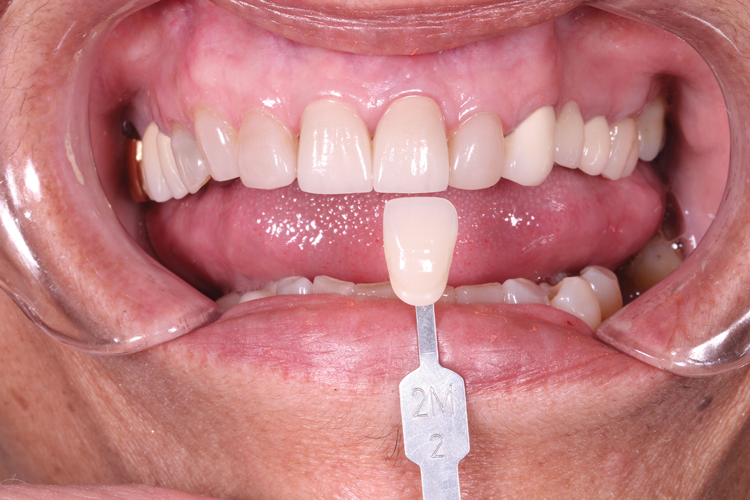

(2.) A composite shade was selected for the tooth to be replaced.

Figure 2